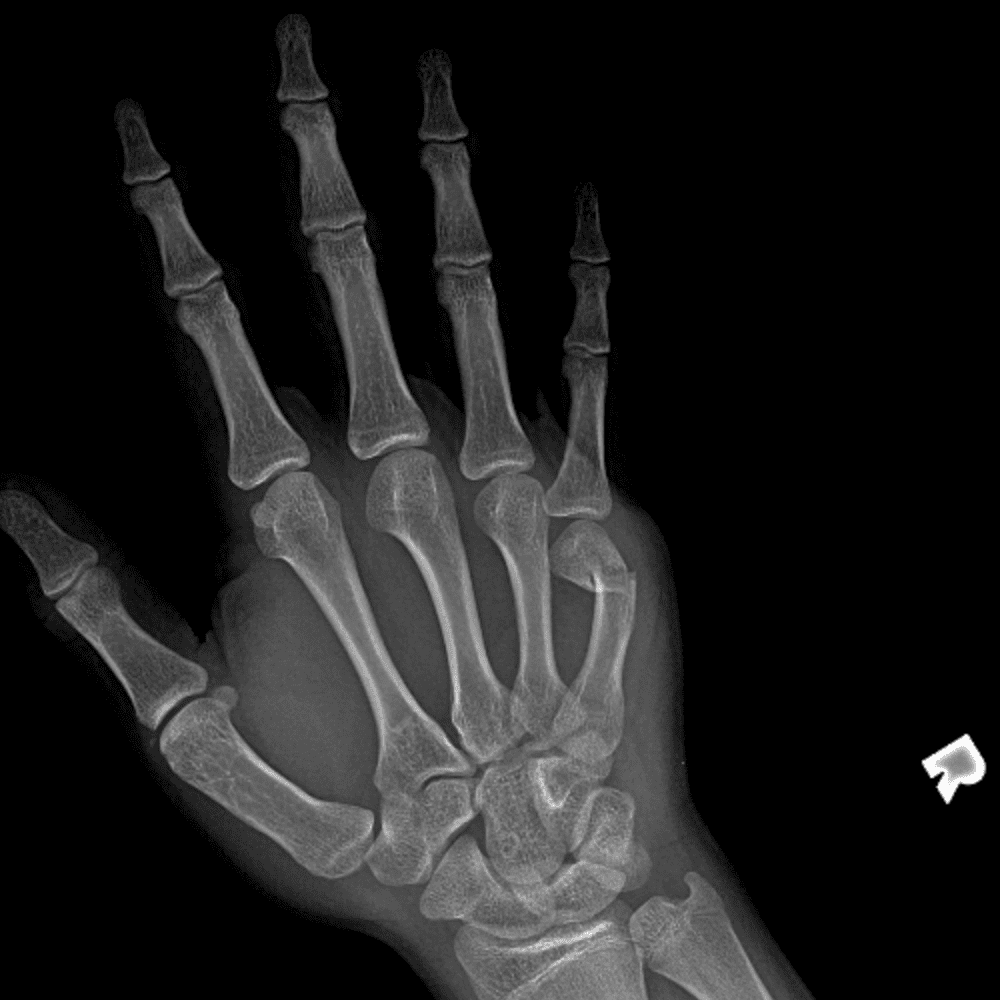

Simulates call by including subtle or difficult cases and some normals.

30 cases